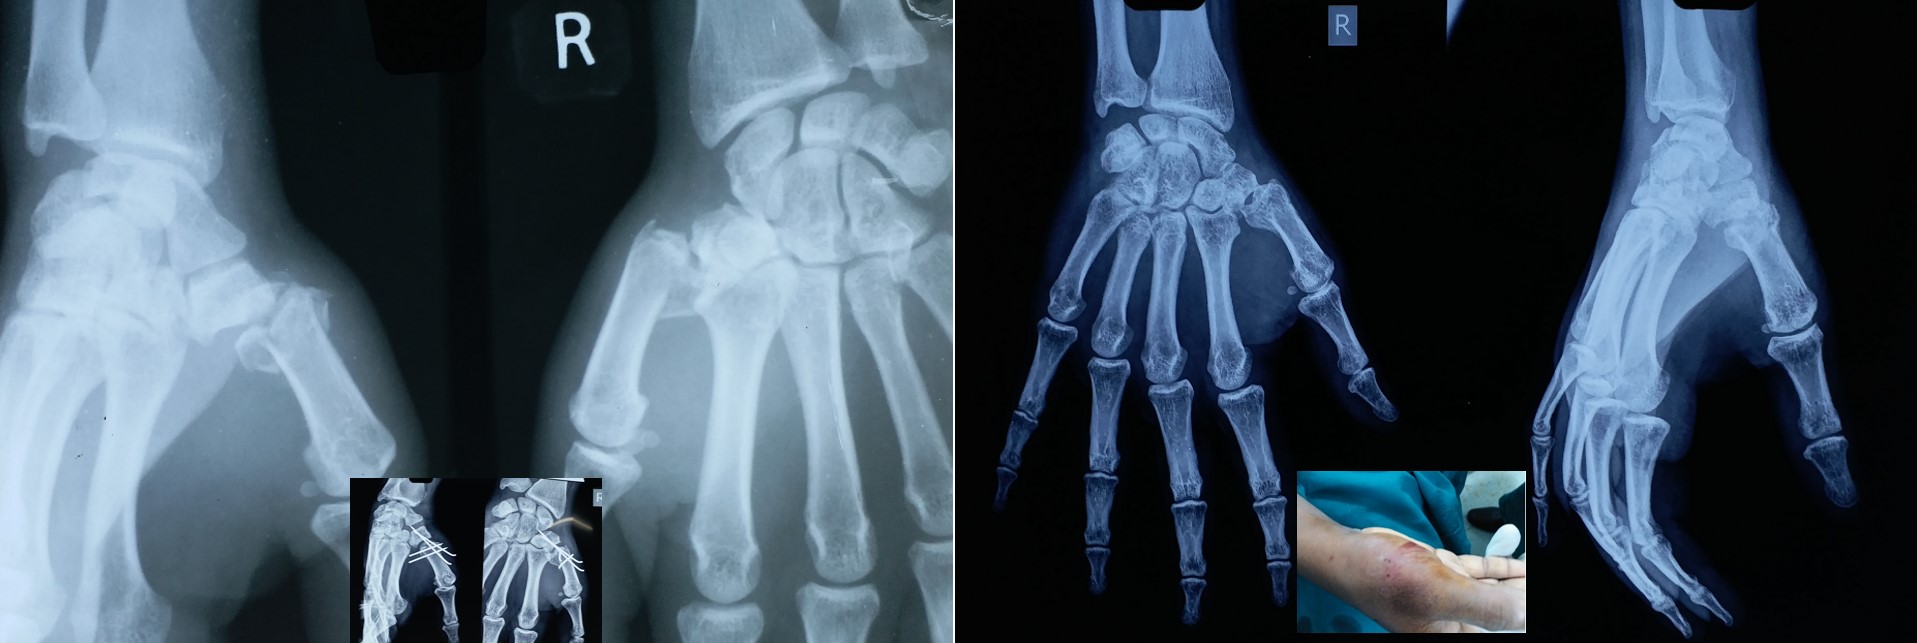

CRPP ( Closed Reduction Percutaneous Pinning )

• No skin incision is required, and fracture heals faster than open surgeries as there is no iatrogenic soft tissue damage or disturbance to the fracture hematoma.

• No implants projecting outside the skin and hence painless adjacent joint movement is possible immediately after CRPP.

• Most of the metaphyseal fractures of both upper and lower limbs can be successfully treated by CRPP.

• It can be applied to any intraarticular fractures, distal end radius, elbow, ankle and foot.

• Early return to some of the personal works like writing, dressing, washing etc from the 2nd postoperative day onwards after CRPP of the fracture distal radius.